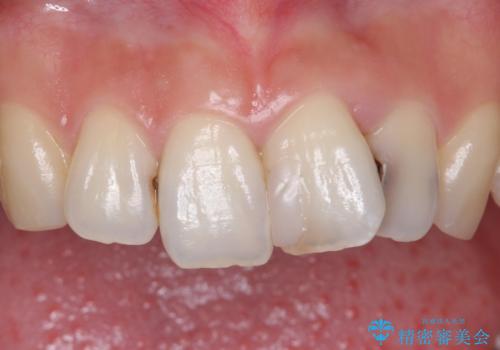

前歯をきれいにしたい 20代女性

- 前歯をきれいにしたいとのご希望により来院された患者様です。

ご希望により、上の前歯4本のセラミッククラウンによる補綴治療を行いました。